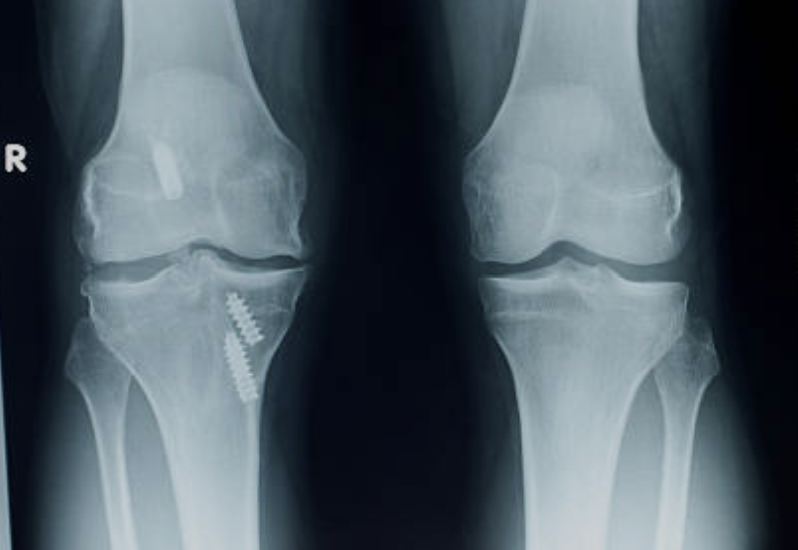

십자인대 파열 증상 원인 치료방법 알아봐요. 십자인대는 무릎 관절 내부에 있는 크로스밴드로, 대퇴골과 정강이 사이를 가로지르며 무릎 관절을 유지하는 중요한 역할을 합니다. 하지만 외상이나 나이, 비만 등으로 인해 손상되면 무릎 통증, 불안정성, 굽힘 및 펴짐 제한 등의 증상이 나타납니다. 큰 부상이 없어도 반복적인 무릎 부하나 체중 등에 의해 부담을 받는 경우에도 손상이 생길 수 있으며, 무릎 관절을 지지하는 인대 중에서는 가장 높은 부상률을 가지고 있습니다. 처치하지 않으면 불안정한 무릎 관절이 발생하며, 장기적으로는 무릎 관절염이나 연골손상 등을 초래할 수 있기 때문에 증상이 나타나면 적절한 치료가 필요합니다.

십자인대는 무릎 관절을 안정시키는 중요한 조직 중 하나로, 만일 십자인대가 파열된다면 무릎을 움직이는데 큰 문제가 발생할 수 있습니다. 십자인대 파열의 초기 증상으로는 무릎 부위에 갑작스러운 통증이 느껴지는 경우가 많습니다. 이어서 부종이나 출혈, 무릎 관절 부근 부분의 압력감 또한 느껴질 수 있습니다. 걷거나 달리는 등 일상적인 활동이 어려워지며, 무릎 관절 근육이 약해져 근육 긴장도나 균형감각 또한 떨어지는 경우가 있습니다. 만약 십자인대 파열이 심한 경우, 무릎 관절이 불안정해져 엉덩이나 무릎 부상의 위험성이 높아질 수 있습니다. 이로 인해 무릎 관절이 불균형하게 움직이면서 연골이 마모되고 골관절염 등의 문제가 발생할 가능성이 높아집니다.

십자인대 파열은 수술적 치료를 필요로 하는 중대한 부상으로, 적절한 치료 방법이 중요합니다. 대부분의 경우, 수술 전 물리치료와 처치가 시작됩니다. 다음은 십자인대 파열 치료 방법의 일부입니다.

1. 수술: 십자인대 파열이 심각한 경우 수술이 필요합니다. 수술 방법은 파열의 위치, 크기 및 환자의 개인 상황에 따라 달라집니다. 대표적인 수술 방법으로는 십자인대 재건술, 십자인대 대체술 등이 있습니다.